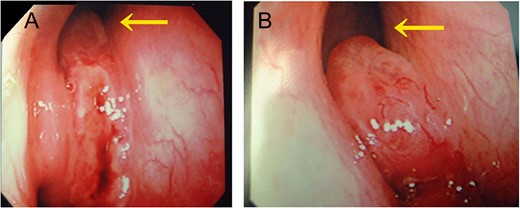

A 57-year-old man with a chief complaint of right nasal obstruction and hemorrhage was referred to our department for detailed examination. His own and family histories were unremarkable. Nasal endoscopy showed a readily bleeding mass between the right nasal septum and inferior turbinate (Fig. 1A). Enhanced CT (Fig. 2) revealed a heterogeneous mass lesion (5 × 1.7 cm) with an enhancement effect that filled the right nasal cavity. The nasal septum and lateral nasal wall were not deformed. Soft-tissue density was observed in the right ethmoid sinus, but was thought to be a mucous thickness due to its difference from the tumor’s density. The tumor evidenced an equivalent signal in the T1 and T2 weighted images of MRI with a strong enhancement effect.

Endoscopic view of the right nasal cavity. (A) Before and (B) after rIL-2 administration. After rIL-2 administration, the tumor size was reduced (arrow).

We recommended a surgical resection as the therapy of choice, but the patient did not agree. Therefore, we decided to use rIL-2 which had been effective in a previous patient of ours with HPC of the maxillary sinus [6]. rIL-2 was given at a dose of 350 000 IU/day intravenously for 15 days, and a dose of 700 000 IU/day (twice a day) for more 5 days. No side effects such as fever elevation or eruption were seen. Nasal endoscopy showed that the pedicle of the tumor had become clearer because its size had been reduced (Fig. 1B). CT revealed a 46% size reduction (two-dimensional measurement) of the tumor. This result nearly corresponds to a partial response. However, since it was impossible to eliminate the tumor completely, the patient finally agreed to the operation.